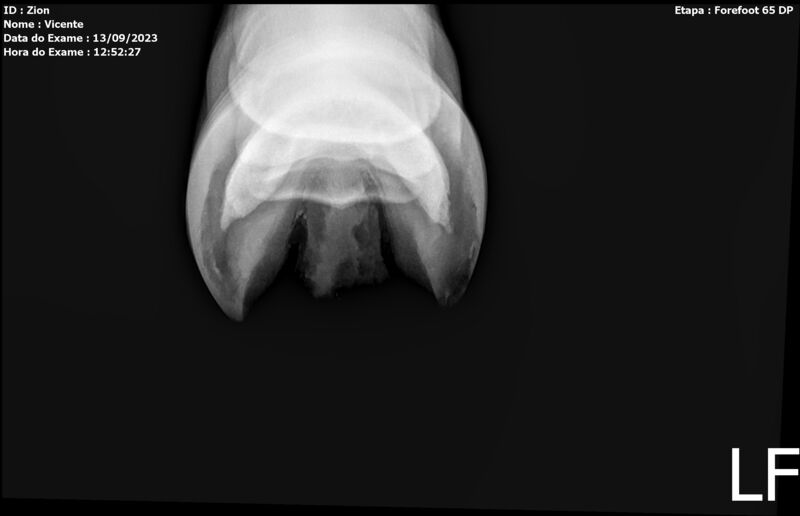

ZION ZC

Raça: BRASILEIRO DE HIPISMO

Sexo: MACHO - POTRO

Nascimento: 17/12/2022

Altura Aproximada: 1,51

Pel.: CASTANHO

Registro: EM AND

Vend.: VICENTE CONTE

Local : PORTO FELIZ/SP